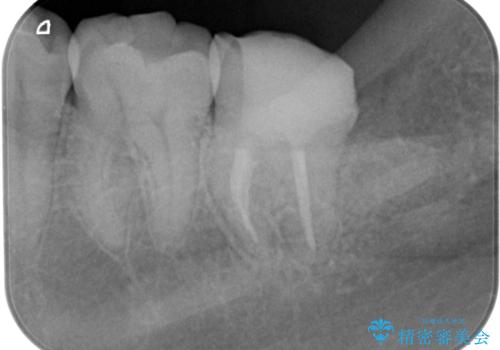

神経をとる処置をされた形跡がありましたがまだ虫歯が残っていたので全て取り除き、壁を立てて根管治療ができる状態にして、根管治療・ジルコニアクラウンで治療を行いました。

- ジルコニアクラウン・仮歯 12.1万円 根管治療(イニシャル)・ファイバーコア 13.2万円費用は治療当時の料金となります

虫歯除去、根管治療は拡大鏡やマイクロスコープを用いて治療を行っています。